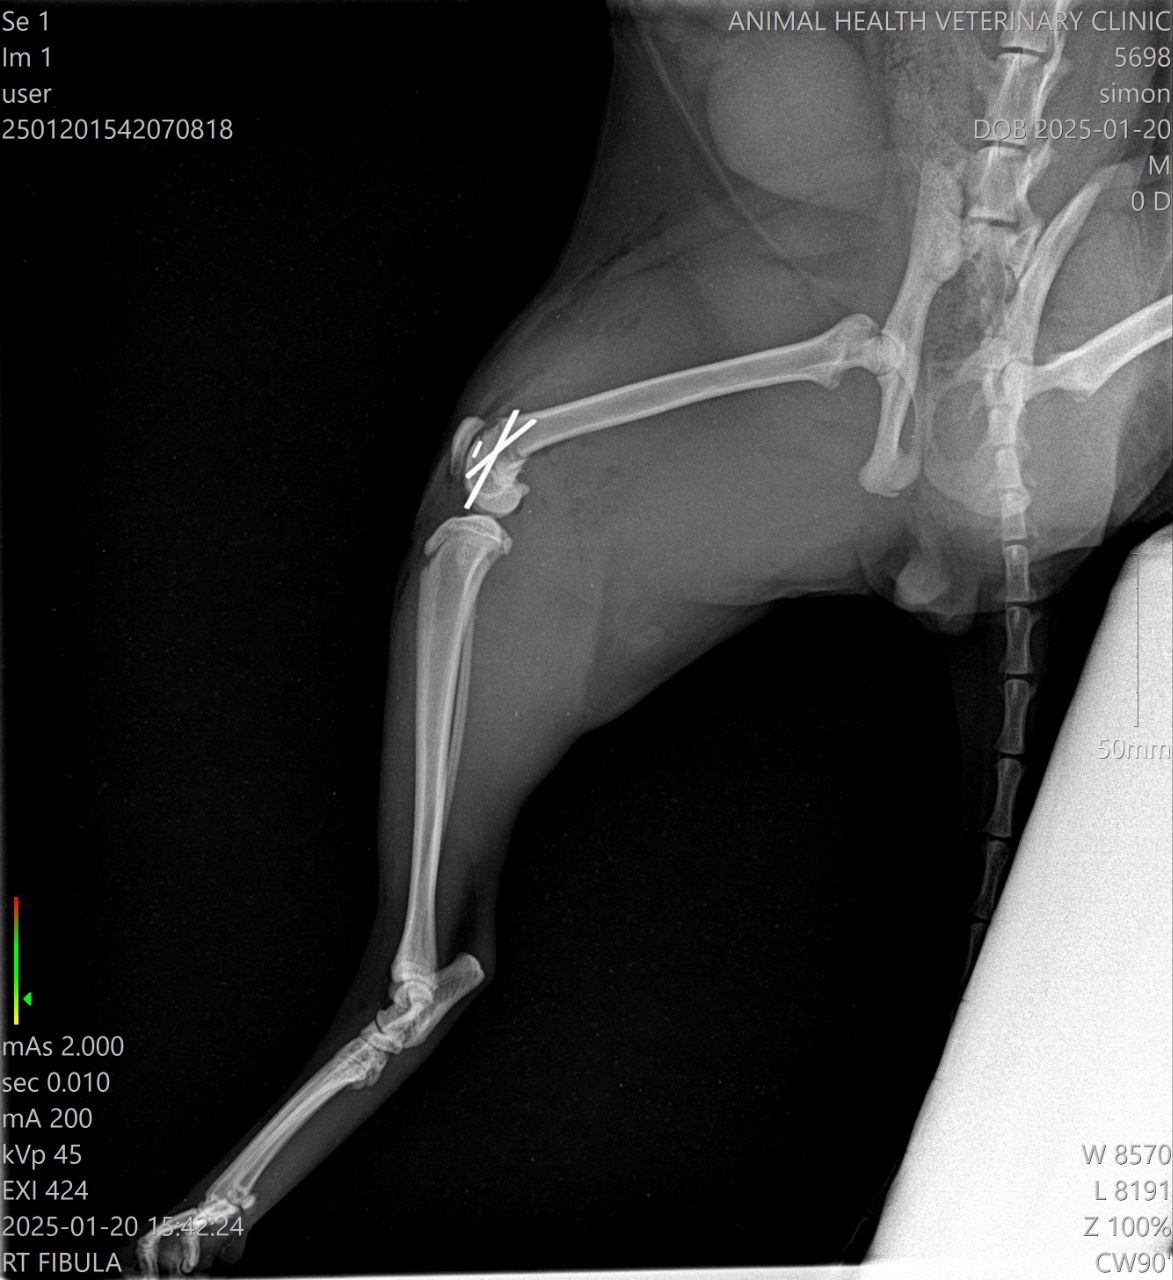

Перелом бедренной кости, требуется операция. В остальном здоров и бодр, ест, пьёт, ходит в туалет.

Тут закрытый перелом не кости а коленного сустава, сильно выраженная бронхиальная картина. Антибиотик нужен

Он писает? На снимке мочевой как дыня переполнен

Сёму прооперировали, теперь щеголяет бритой ногой, внутри которой крутые спицы. Отойдя от наркоза, стал бодр и ласков, как всегда, и уже на передержке.